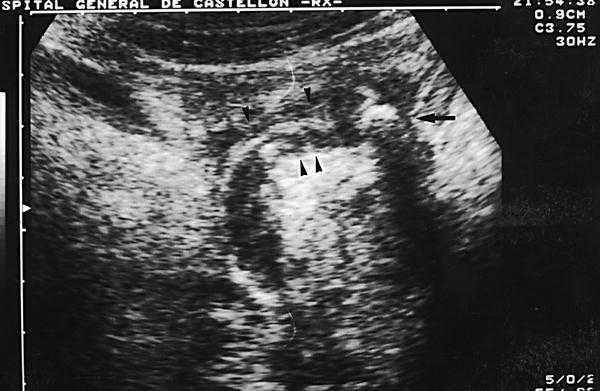

Se solicitó de urgencias, una radiografía simple de abdomen (fig. 1) en la que se observó una imagen densidad calcio, en capas concéntricas, proyectada sobre fosa ilíaca derecha, compatible con apendicolito, tras la cual se decidió solicitar una ecografía abdominal y de fosa ilíaca derecha (fig. 2), en la que se evidenció la existencia de un asa fija, aperistáltica, con su base en el ciego, que terminaba en dedo de guante, dolorosa a la presión y que media más de 6 mm, con una distribución en capas de ecogenicidad alternante y con imagen cálcica en su extremo distal, hallazgo que posteriormente se confirmó con la tomografía computarizada (TC) abdominopélvico (fig. 3). Por todo ello se realizó el diagnóstico de apendicitis aguda catarral-flemonosa, con apendicolito distal.

Fig. 1